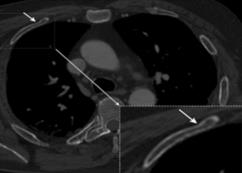

Rib fractures are a common and potentially severe injury that can be challenging and labor-intensive to detect in CT scans. While there have been efforts to address this field, the lack of large-scale annotated datasets and evaluation benchmarks has hindered the development and validation of deep learning algorithms. To address this issue, the RibFrac Challenge was introduced, providing a benchmark dataset of over 5,000 rib fractures from 660 CT scans, with voxel-level instance mask annotations and diagnosis labels for four clinical categories (buckle, nondisplaced, displaced, or segmental). The challenge includes two tracks: a detection (instance segmentation) track evaluated by an FROC-style metric and a classification track evaluated by an F1-style metric. During the MICCAI 2020 challenge period, 243 results were evaluated, and seven teams were invited to participate in the challenge summary. The analysis revealed that several top rib fracture detection solutions achieved performance comparable or even better than human experts. Nevertheless, the current rib fracture classification solutions are hardly clinically applicable, which can be an interesting area in the future. As an active benchmark and research resource, the data and online evaluation of the RibFrac Challenge are available at the challenge website. As an independent contribution, we have also extended our previous internal baseline by incorporating recent advancements in large-scale pretrained networks and point-based rib segmentation techniques. The resulting FracNet+ demonstrates competitive performance in rib fracture detection, which lays a foundation for further research and development in AI-assisted rib fracture detection and diagnosis.